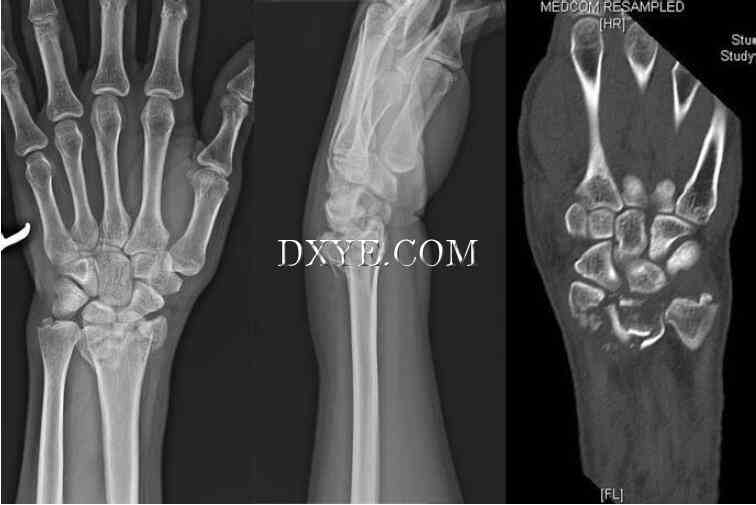

影像学评估。 除了标准的PA和手腕的侧面视图之外,还应该获得45°前倾斜视图和PA握拳尺度偏差(图76.20)。 尺骨的偏差使舟骨处于延伸的姿势,并使其更加完整。 紧握的拳头会突出任何一个舟骨函数扩大和分散任何不稳定的骨折片段。

在最初的X射线上,约8%至20%的舟骨骨折不明显。如果临床怀疑较高,但没有骨折的影像学证据,则应用拇指人字石膏,并在10-14天后进行随访X光片。这可能显示骨折部位的骨吸收。如果平片仍然是阴性,可以考虑骨显像,CT扫描或MRI。虽然骨显像是敏感的,但它是非特异性的,增加摄取可能表明关节病或滑膜炎。 CT扫描对评估骨性解剖结构较好;平行于舟骨长轴的2mm矢状切口是理想的。 MRI可用于检测隐匿性舟骨骨折,评估血管,特别是延迟愈合或骨不连,并排除任何相关的韧带损伤。在T2图像上,急性舟骨骨折骨折线表现为低信号强度,周围骨髓信号强度高。在T1和T2图像上近端AVN明显为暗信号强度。钆增强可以改善近端血管的MR评估。

20.jpg

图 76.20.  舟状视图显示舟骨移位腕骨骨折。

手术治疗。 赫伯特和费希尔1984年引进的无头加压螺钉,已成为舟骨骨折手术治疗方法公认的标准。 这种技术的最大优点是螺钉可以在关节软骨下方凹陷。 使用空心无头螺钉和更好的仪器以及改进的术中透视技术的技术进步使螺钉的放置更容易。

螺杆可以放置在手背或手掌的方法通过一个开放的技术和经皮穿刺技术(图76.22)。背侧开放的方法提供了更好的近端磁极暴露,并允许更容易螺钉放置,但有破坏脆弱的背侧血供应的风险。手掌打开的方法保留了血液供应,但会破坏桡腕韧带和提供的近极差的曝露。为了减少驼背畸形,需要撬起塌陷的舟状骨,并用皮质骨移植支架恢复舟骨长度。经皮技术是用于无移位或轻度移位的骨折患者,避免损伤或韧带的血液供应。结合腕关节镜检查,以确保解剖复位,并发现任何伴随韧带损伤。无论采用何种方法,舟骨螺钉固定的重要方面是将螺钉置于舟骨长轴。当插入螺钉时,认识到舟骨的长轴倾斜大约45°和45°是重要的。

22.jpg

图 76.22.  腕舟骨骨折。 A. 腕舟骨骨折术前X线片(箭头)。 B. 无头空心螺钉切开复位内固定治疗腕舟骨骨折。